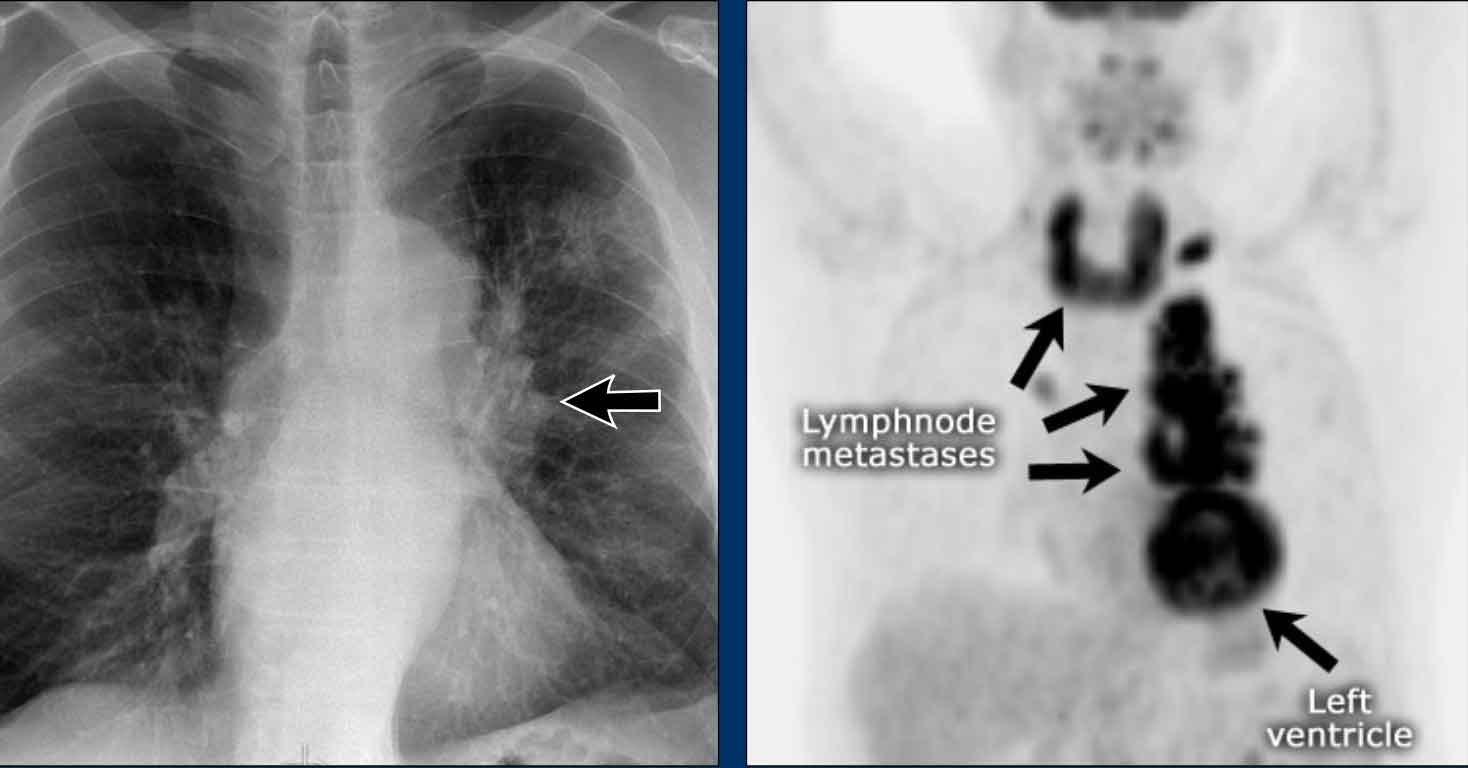

Displacement of the Azygoesophageal Line (2) – Subcarinal Lymphadenopathy

A common cause of displacement of the azygoesophageal line is subcarinal lymphadenopathy (station 7).

On the chest X-ray, note superior displacement of the azygoesophageal line just below the carina, consistent with enlarged subcarinal lymph nodes (black arrow).

Additional right paratracheal lymphadenopathy is seen, displacing the right paratracheal stripe (white arrow) and deviating the trachea to the left.

Continue with PET-CT...

PET Imaging

- PET-CT demonstrates extensive hypermetabolic lymphadenopathy in the mediastinum and neck, which is more conspicuous than on chest radiography.

- Cervical lymph nodes are involved—an important finding as they are accessible for biopsy.

Continue with images of CT and ultrasound...

CT Imaging

- Contrast-enhanced CT shows bulky subcarinal lymphadenopathy displacing the azygoesophageal recess and compressing the left atrium.

- Biopsy of a cervical node confirmed small cell lung carcinoma.